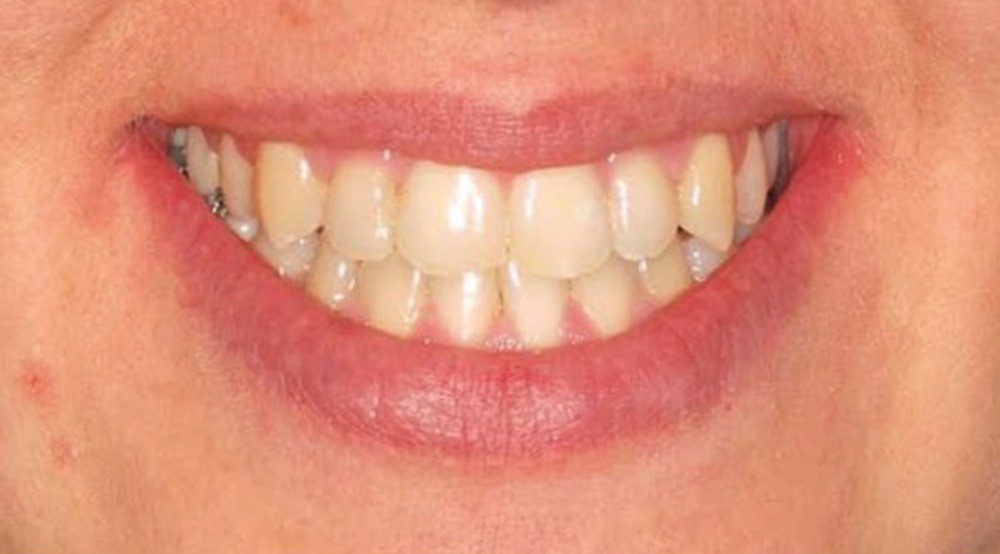

C’est à ces questions que nous permettront de répondre les deux premiers conférenciers, parodontologistes : le Dr Béatrice Straub nous présentera le renfort parodontal minéralisé, technique qu’elle a développée et pratique depuis de nombreuses années, pour éviter les préjudices des mouvements orthodontiques à risque, notamment lors des décompensations préchirurgicales (fig. 1a-d) ; le Pr Anton Sculean abordera le thème des greffes, avec leurs indications, les différentes techniques à privilégier et illustrera ses propos par de nombreux cas cliniques aux résultats esthétiques impressionnants.